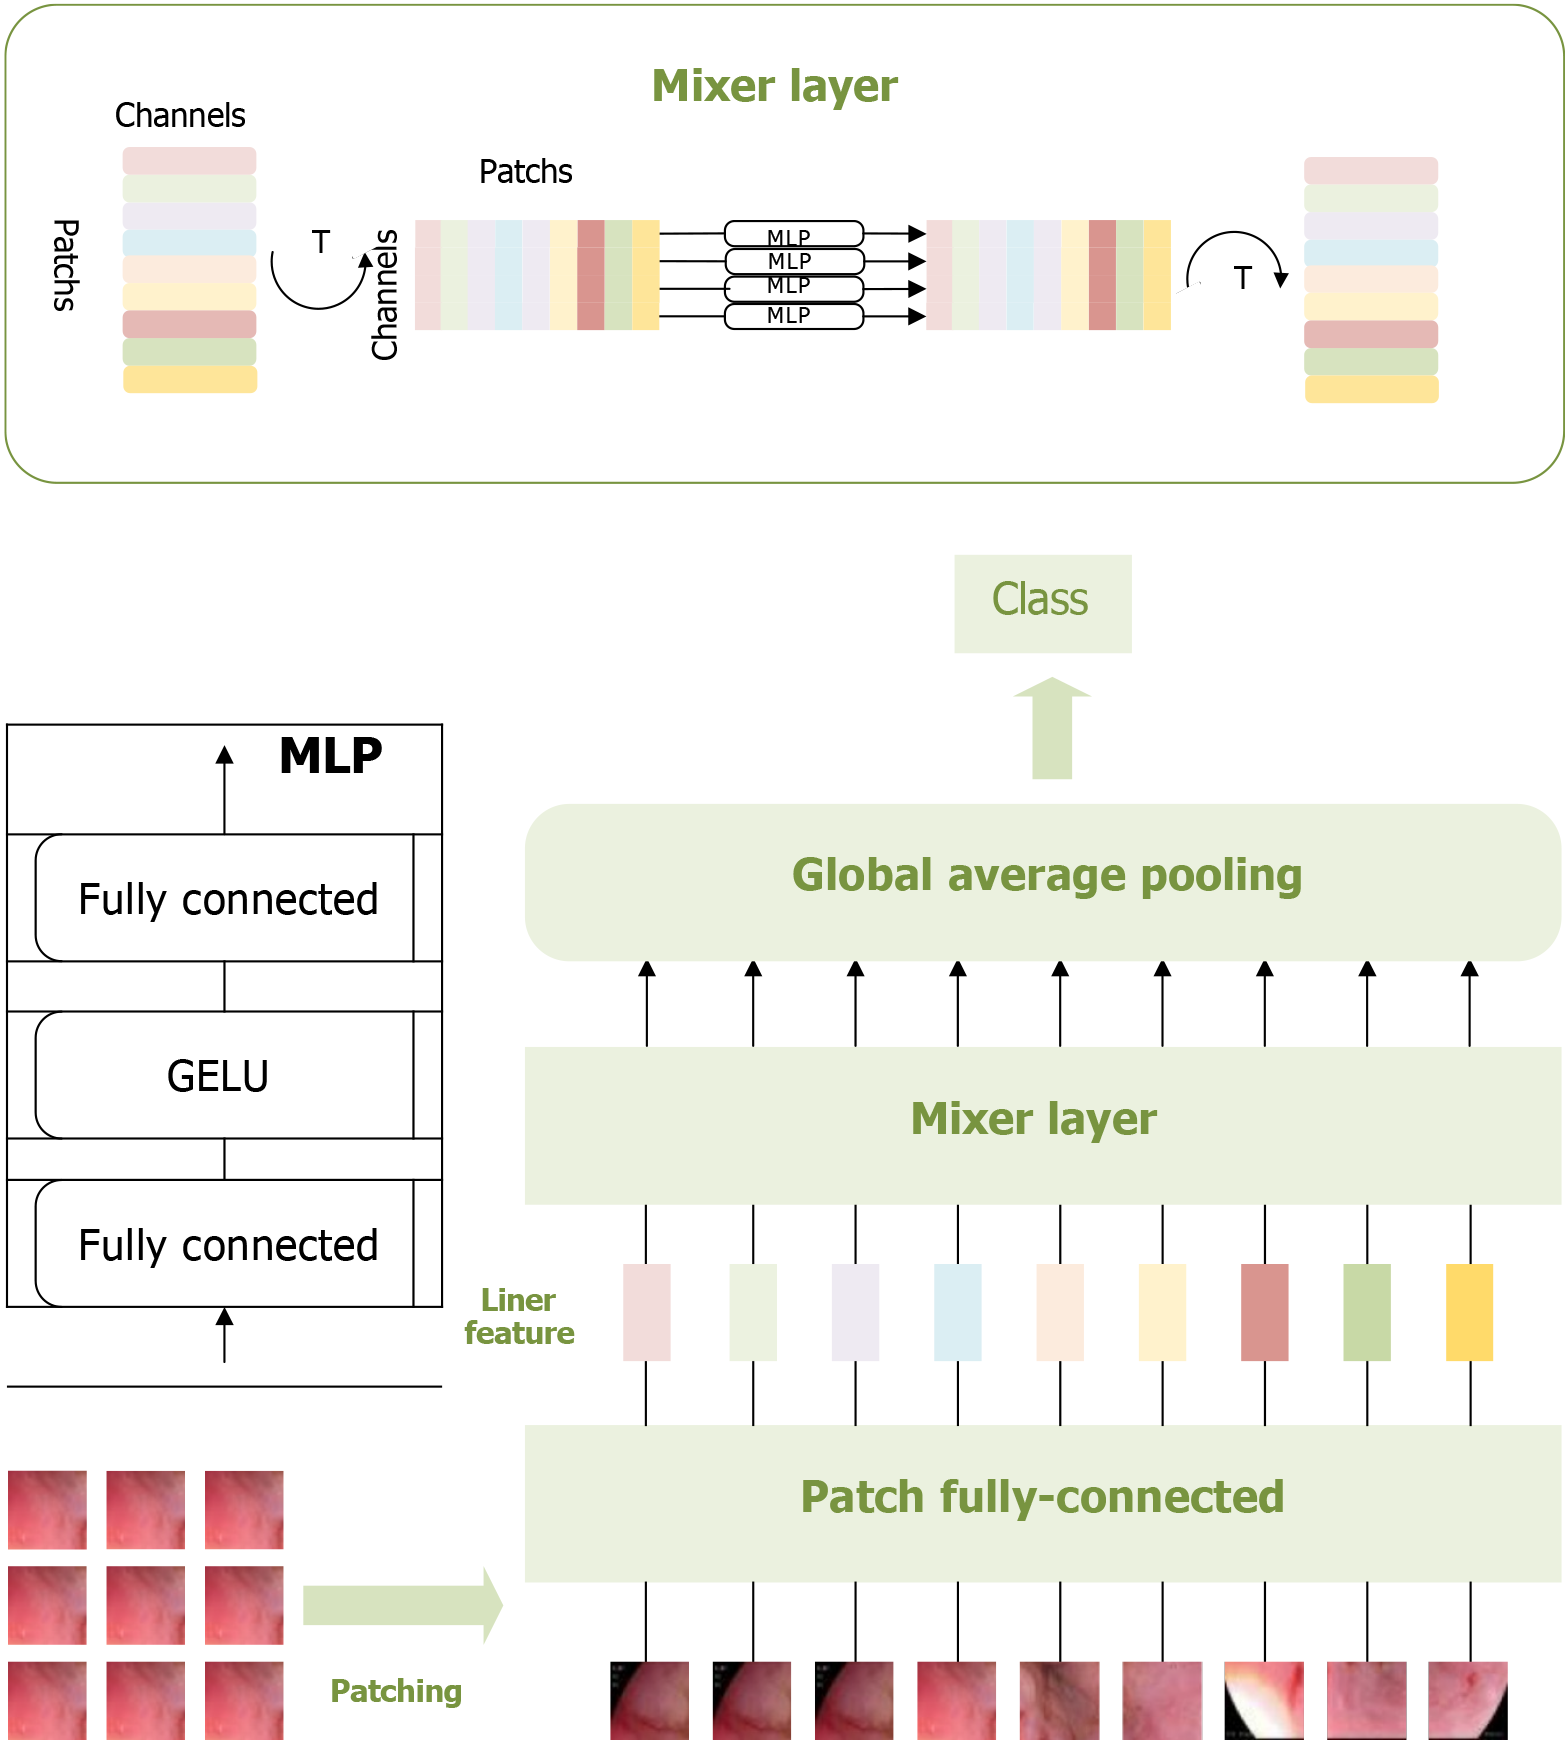

To fully leverage the potential of MLP, Tolstikhin et al[32] developed an upgraded model called the MLP-mixer, a purely MLP-based architecture. The MLP-mixer comprises two types of layers: One type of MLP operates independently on each image patch, mixing features at each location, while the other type applies MLP across patches, mixing spatial information. The application of the MLP-mixer model on the dataset in this study is illustrated in Figure 2.